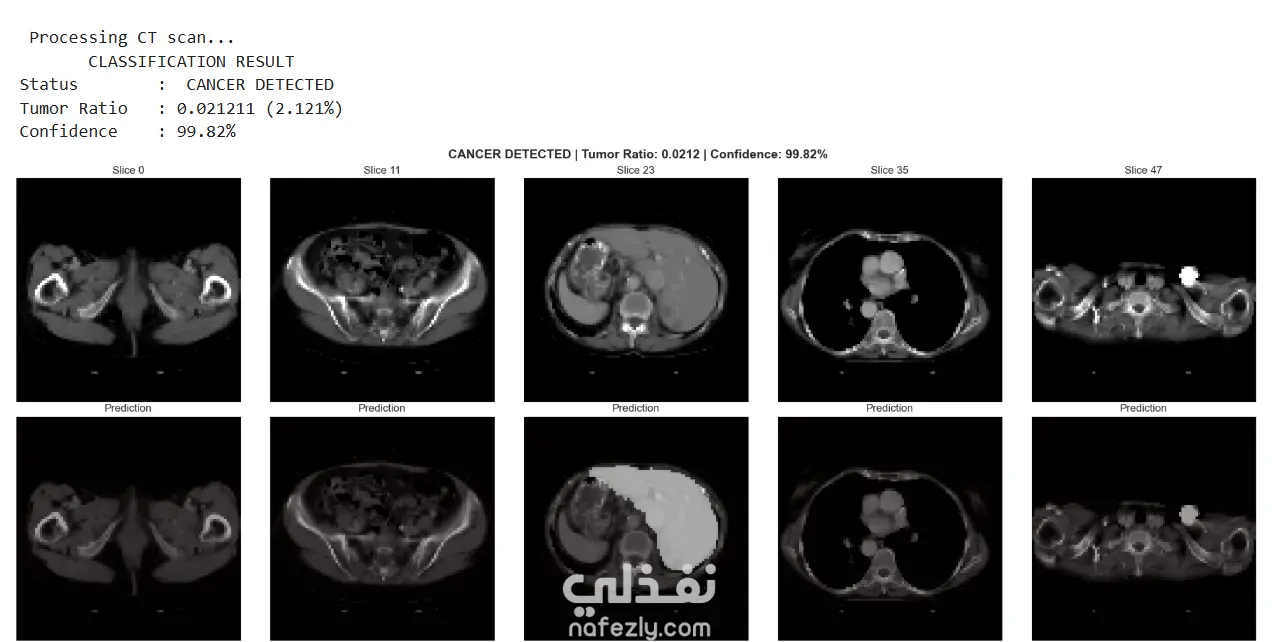

1. Overview This project presents an end-to-end medical AI solution designed to automate the detection and segmentation of liver tumors from 3D Computed Tomography (CT) scans. By utilizing state-of-the-art Deep Learning techniques, the system assists radiologists in identifying cancerous tissues and calculating tumor-to-liver volume ratios with high precision. 2. Technical Methodology The core of the system is an Improved 3D U-Net architecture, enhanced with several modern optimizations: Residual Connections: Integrated to improve gradient flow and allow the model to learn more complex features during training. Mixed Precision Training: Utilizes float16 for computations to significantly speed up training and reduce GPU memory consumption. Advanced Preprocessing: Implements Hounsfield Unit (HU) windowing (clipping between -100 and 400 HU) to isolate soft tissue and normalize intensities for better model convergence. Memory Efficiency: Features a custom data generator with caching and dynamic batch sizing to handle heavy 3D NIfTI files without overloading system memory. 3. Key Features Dual-Purpose Output: The model performs Segmentation (pixel-wise tumor mapping) and Classification (diagnosing "Cancer Detected" vs. "No Cancer" based on tumor ratio). Combined Loss Function: Uses a blend of Binary Crossentropy and Dice Loss to tackle the class imbalance problem inherent in medical imaging (where tumors are small compared to the whole scan). Comprehensive Visualization: Includes a full pipeline to visualize raw scans, resized masks, and final overlays across multiple 3D slices. Reliability Metrics: Evaluates performance using the Dice Coefficient, a standard in medical imaging to measure the overlap between the ground truth and the model's prediction. 4. Practical Application The final model is capable of processing new NIfTI files, providing a diagnostic status, a tumor-to-liver ratio, and a confidence score. This serves as a vital Computer-Aided Diagnosis (CAD) tool, reducing the manual workload for medical professionals and increasing the accuracy of early cancer detection.